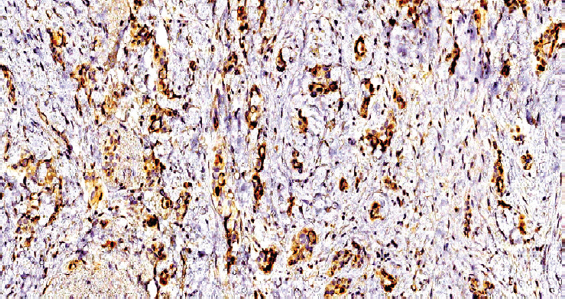

Results. In the group of triple negative breast cancer, 4 cases were detected expressing a cow leukosis virus antigen. Expression was represented by grains and clumps in the cytoplasm and on the surface of the tumor cell membrane, the wall of microvessels. Also in these cases, increased expression of VEGF was detected.

Conclusion. The results indicate that expression of the BLV antigen was observed only in cases of poorly differentiated triple negative breast cancer. It is also noteworthy that the same type of BRCA1 gene mutation (5382insC) and increased expression of vascular endothelial growth factor were detected in these tumors. The authors first used the immunohistochemical method for detecting the antigen of the BLV virus, which made it possible to reliably confirm its presence in breast tumors with similar molecular genetic and immunohistochemical profiles.